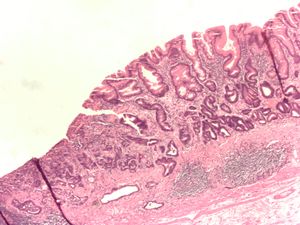

ـ التنطير الهضمي والخزعة: مع التطور الكبير في مجال صناعة المناظير الضوئية الليفية المرنة flexible fiberoptic endoscopes، صار من السهل إجراء فحص كامل ودقيق لمخاطية المعدة، ومشاهدة التغيرات المرضية، ومنها سرطان المعدة، مباشرة، وكذلك أخذ خزعات متعددة منها من أجل التشخيص النسيجي. ويجب أخذ 4 إلى 6 خزعات من أي آفة مشبوهة في المعدة لرفع دقة التشخيص.

يساعد التنظير الهضمي أيضاً على تحديد مكان الآفة في المعدة، ويمكن باستخدام التصوير بالأمواج فوق الصوتية خلال التنظير endoscopic ultrasound دراسة مدى ارتشاح الورم في جدار المعدة، ومن ثم التفريق بين سرطانات المعدة الباكرة والمتقدمة بدقة تصل إلى نحو 80%.